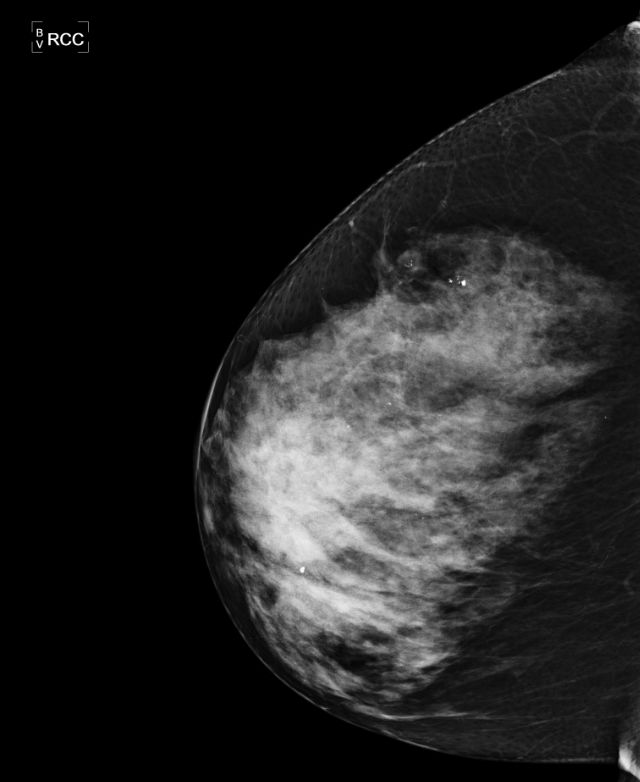

Mamma und axilläre LK |

71-jährige Frau mit diffuser Schwellung und

Rötung der rechten Brust.![]() |

großer axillärer Lymphknoten erkennbar.![]() |

CT: Lymphknoten rechts axillär.![]() | ||||